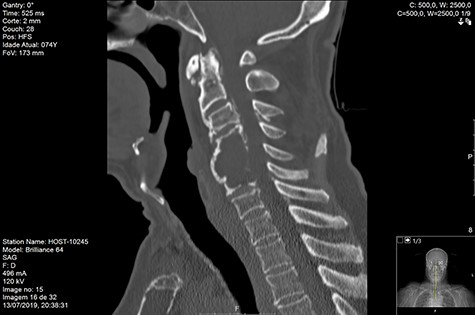

Computed tomography (CT) (Figs 1–3) and magnetic resonance imaging (MRI) (Figs 4–6) of the cervical spine were performed and revealed a lytic lesion involving most of C4, C5 and C6 vertebral bodies with bilateral extension to the posterior spinal elements of C4 and C5 and complete disruption of C4-C5 and C5-C6 intervertebral discs.

The Spinal Instability Neoplastic Score (SINS) [4, 6, 7] for assessing spinal instability from metastatic disease was used and the lesion was deemed unstable (SINS 13), with impending risk of increased neurological damage.

Findings from laboratory tests (serum protein electrophoresis) led to the diagnosis of MM. The patient was placed on a Philadelphia c-spine collar and underwent local 3D external-beam radiotherapy (20Gy in five fractions).